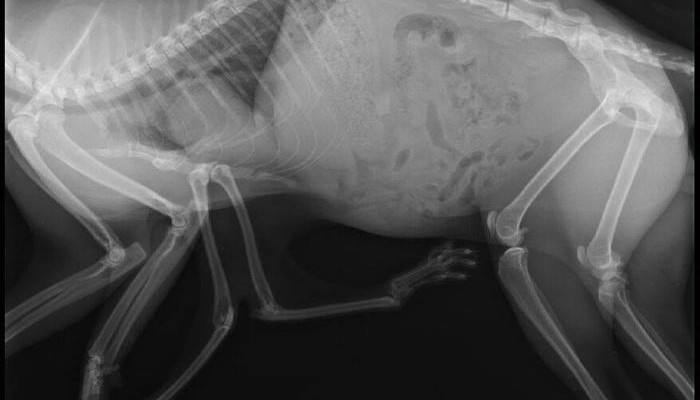

Pauly vive a Edmonton in Canada e ha sei zampe… non ci potete credere!?

In effetti, si tratta di una patologia rarissima che colpisce un gatto su 10mila. È stato trovato lo scorso aprile nella parte sud-ovest della città da alcuni cittadini che lo hanno aiutato e hanno contattato l’associazione animalista Little Cats Lost che lo ha subito accolto.

Secondo i medici la malformazione di Pauly dipende probabilmente dal fatto che dentro l’utero della madre ci fossero due gattini e che uno abbia inglobato l’altro.

Data la grande difficoltà nella deambulazione, un intervento chirurgico è ormai necessario per il gatto che ha già sette anni e presenta una grave displasia dell’anca.